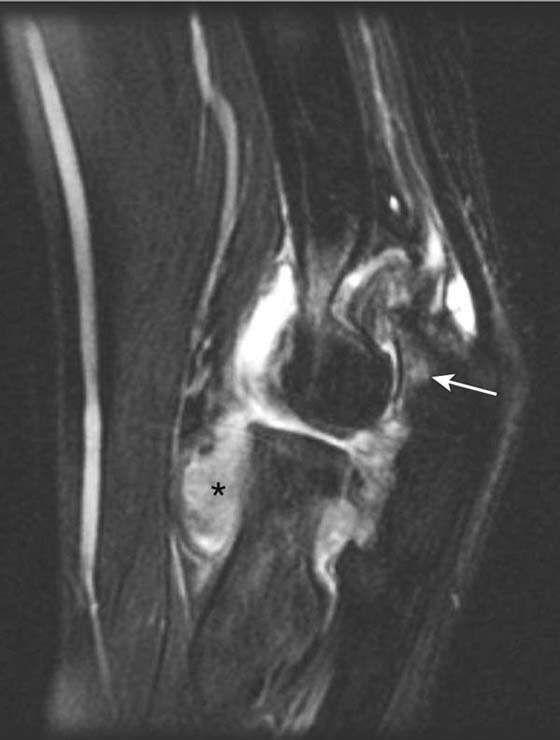

Direct MR arthrography is most useful in detecting suggested injury to the medial and lateral stabilizing ligaments. The medial (ulnar) collateral ligament, for example, is frequently injured in baseball pitchers and can be assessed accurately with MR arthrography34-36 (Fig. 14-13). US is also useful in assessing the elbow ligaments but has an advantage over MRI with its ability to assess ligamentous laxity in real time with dynamic imaging37,38 (Fig. 14-14). For example, during valgus stress for assessment of the medial collateral ligament, a difference in 2 mm between sides is diagnostic of abnormal ligamentous laxity.

images

Figure 14-13 Ulnar collateral ligament tear. Coronal fat-suppressed T1-weighted image of the elbow after intra-articular gadolinium injection (direct MR arthrogram) demonstrates abnormal tracking of contrast (arrow) between the anterior bundle of the ulnar collateral ligament and the coronoid process of ulna at the sublime tubercle, indicating a distal partial thickness undersurface tear.